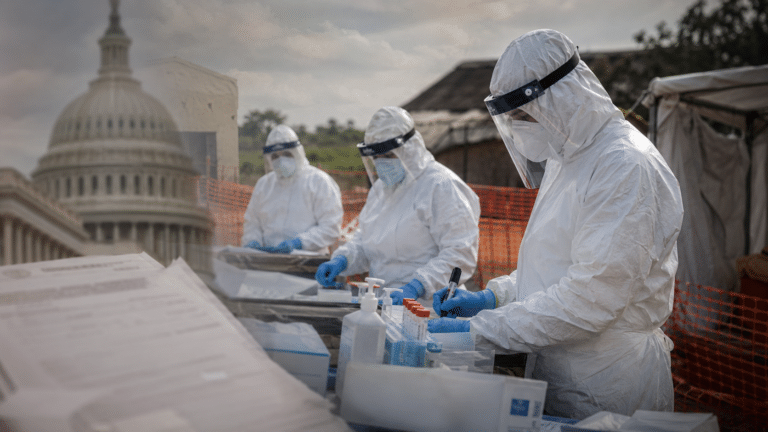

The Trump Ebola funding request would provide more than $1.4…

By – Michallie HarrisonTemperatures in France were higher than…